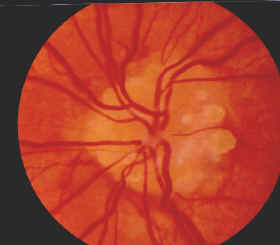

| Drusen im Sehnervenkopf/ Papille (kleine weiße Punkte) | Papille durch das Auge gesehen mit Drusen | normale Papille ohne Drusen | Querschnitt des Auges |

Unter Drusenpapille versteht man kalkartige Ablagerungen im Sehnervernkopf / Papille. Dies ist dort, wo der Sehnerv in den Augapfel gelangt. Diese Drusen können vererbt von Geburt an in der Tiefe vorhanden sein, wachsen dann erst mit dem Alter heraus. Drusen können sich aber auch bilden und vermehren. Da sie auf den Sehnerven drücken, können sie diesen schädigen. Auch die Durchblutung des Sehnerven und der Netzhaut kann erheblich gestört werden. So können die Drusen zu einer erheblichen Einengung des Gesichtsfeldes führen. Auch im zentralen Sehbereich können Drusen anscheinend verschwommenes Sehen und Flimmern auslösen, was dann zu Beschwerden wie Kopfschmerzen führt.

Ich bin 40 Jahre alt. In meinem Fall haben die Drusen auf beiden Augen schon einmal zu einer Art Netzhautstauung geführt, die dann in kurzer Zeit große Gesichtsfeldschäden verursacht hat. Diese war 1993 rechts und 1995 links. Seitdem hat sich mein Gesichtsfeld ganz langsam weiter verschlechtert. Auch beim Lesen habe ich sehr starke Probleme mit Flimmern, verschwommenem Sehen und Kopfschmerzen, was meine Leistungsfähigkeit erheblich einschränkt.

Meine Augenpobleme begannen 1983 nach einem Infekt mit hohem Fieber. Ich klagte über Augeschmerzen. Beim Augenarzt wurde beidseits eine Stauungspapille diagnostiziert.. Das anschließende CT ergab zum Glück nichts. Aber auch Drusen waren damals noch nicht zu sehen. Mir wurde dann nur geraten regelmäßig zum Augenarzt zu kommen. Seitdem habe ich nach geringe Anstrengung der Augen. Beschwerden (starker Druck in Augen und Stirnbereich, Augenbrennen, verschwommenes Sehen): Mit Beginn meiner Ausbildung verstärkten sich die Beschwerden massiv. Ich konnte meinen Arbeitstag nur mit Zähne aufeinander beisen überstehen. Abends war ich dann fix und fertig. Die Augenärzte sagten mir nur, außer einer harmlosen Drusenpapille hätte ich nichts. Bis dann 1993 und 1995 plötzlich die massiven Gesichtsfeldeinbrüche kamen. Durch den Gesichtfeldverlust wurden dann meine Augenbeschwerden noch stärker. Eine leichte Verbesserung machte 2001 eine Brille mit Prismatischer Vollkorektur.